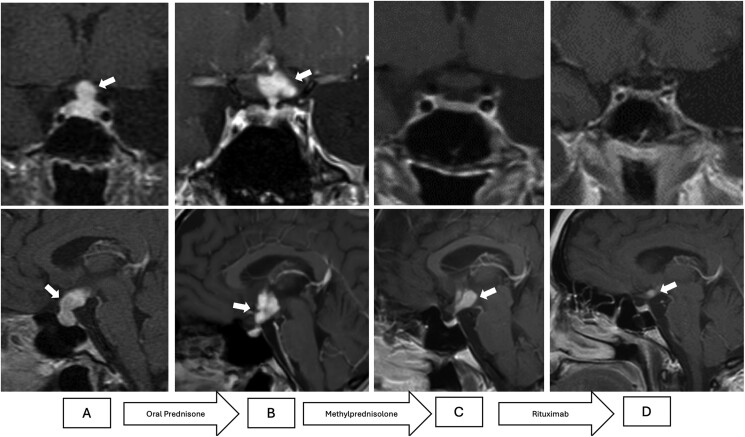

Neurosarcoidosis (NS) is a rare form of sarcoidosis, with isolated hypothalamic-pituitary involvement being exceptionally uncommon. We report a 20-year-old woman presenting with polyuria, galactorrhea, amenorrhea, and substantial weight loss. Hormonal evaluation revealed hypopituitarism with arginine-vasopressin deficiency and hyperprolactinemia. Magnetic resonance imaging demonstrated pituitary stalk thickening and suprasellar extension, initially suggestive of hypophysitis. High-dose glucocorticoid therapy resulted in partial regression of the pituitary lesion but persistence of suprasellar involvement, prompting a transcranial stereotactic biopsy. Histopathological analysis confirmed isolated NS with noncaseating granulomas. The patient was treated with rituximab after partial response to glucocorticoids, achieving significant clinical and radiological improvement, although hormonal axis recovery was not observed. Hormone replacement therapy remains necessary. The case met the criteria for definitive type b NS, as no extraneural involvement was identified. This case underscores the diagnostic challenges of isolated NS and highlights the importance of considering histopathological confirmation in patients without systemic manifestations to guide treatment. Glucocorticoids are first-line therapy, but rituximab may be effective as a second-line option for refractory cases. Early diagnosis and tailored therapy are essential to improving outcomes in this rare and challenging condition.